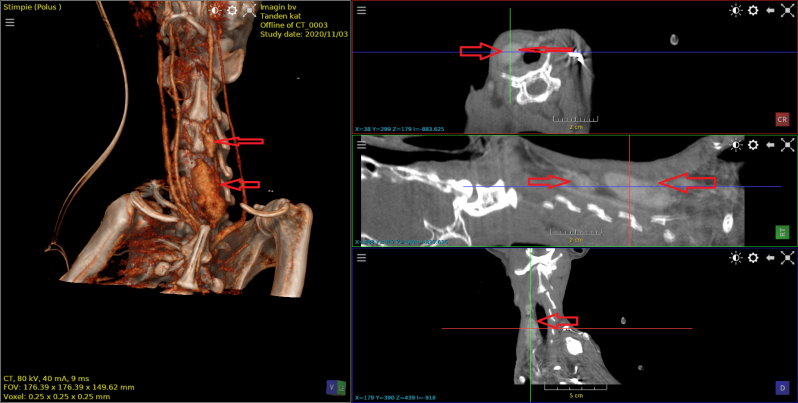

Dalmatier van 11 jaar met verlamming ten gevolge van  discus hernia op de overgang van T13  naar L1.

Eerst beelden van RX,  daarna scan beelden met en zonder contrast , vervolgens 3D beeld.